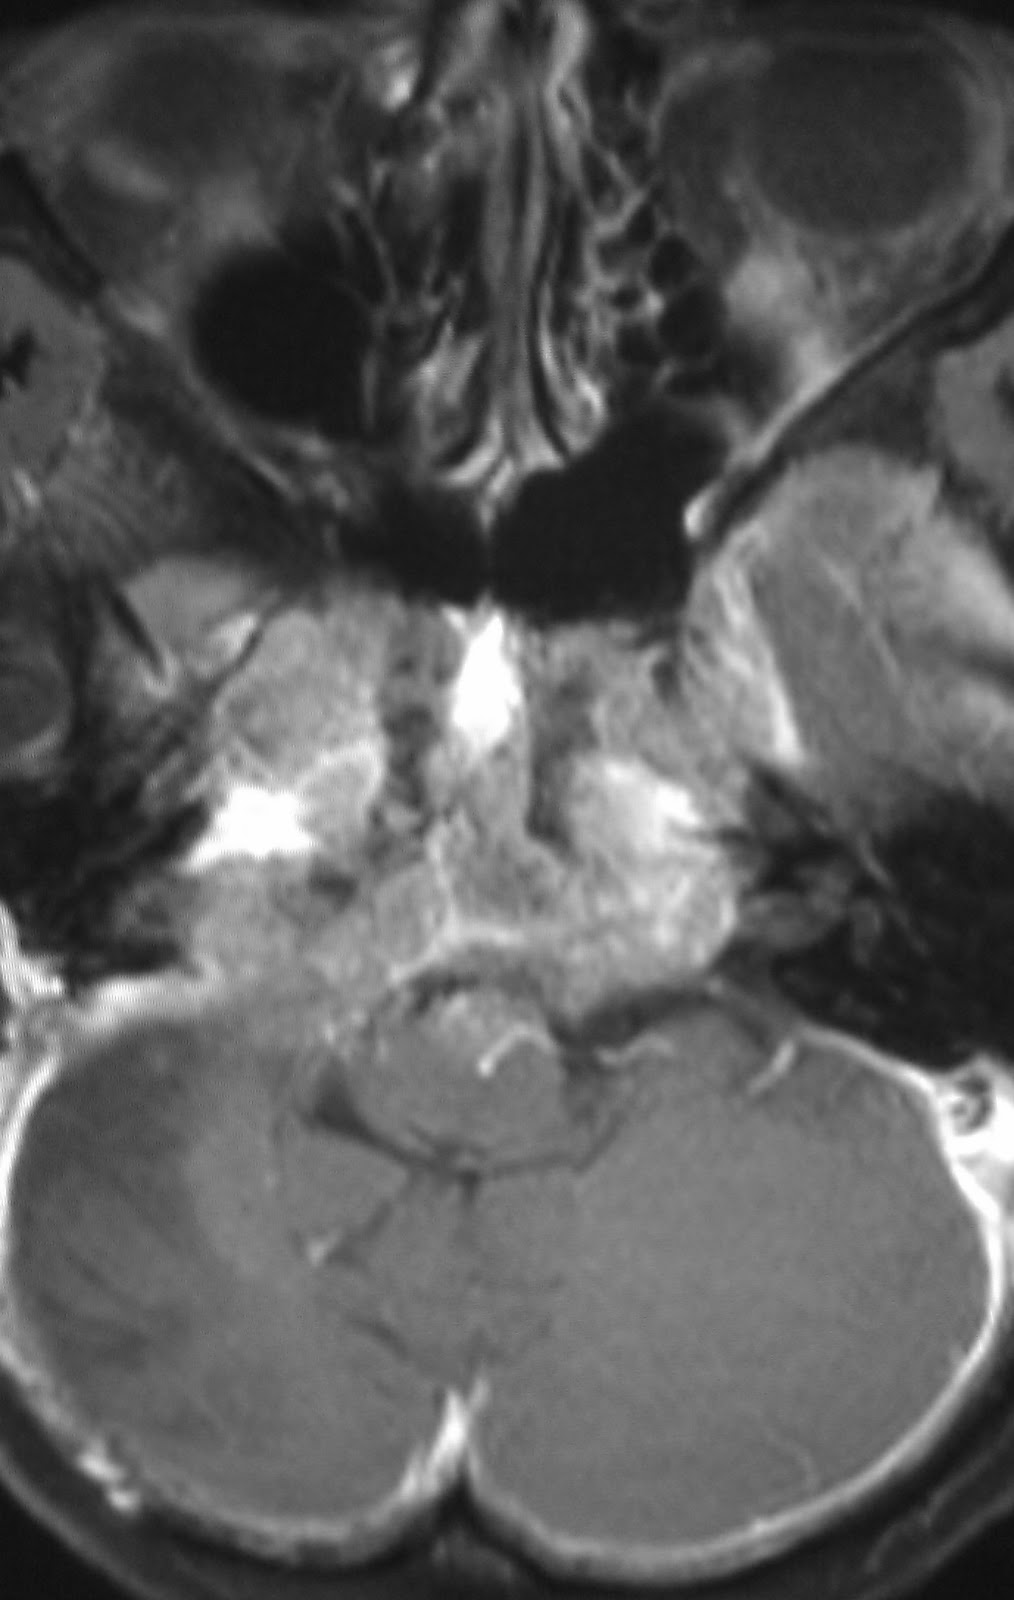

Fourth Ventricle - Wikipedia, The Free Encyclopedia

The fourth ventricle extends from the cerebral aqueduct (aqueduct of Sylvius) to the obex, and is filled with cerebrospinal fluid (CSF). The fourth ventricle is a common location of an intracranial ependymomal tumour. References ... Read Article